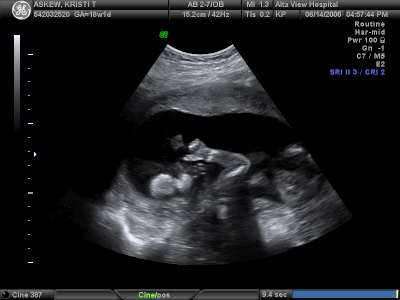

Sucking her thumb

She's like her mommy as a baby. Always had her thumb in her mouth. Yikes!